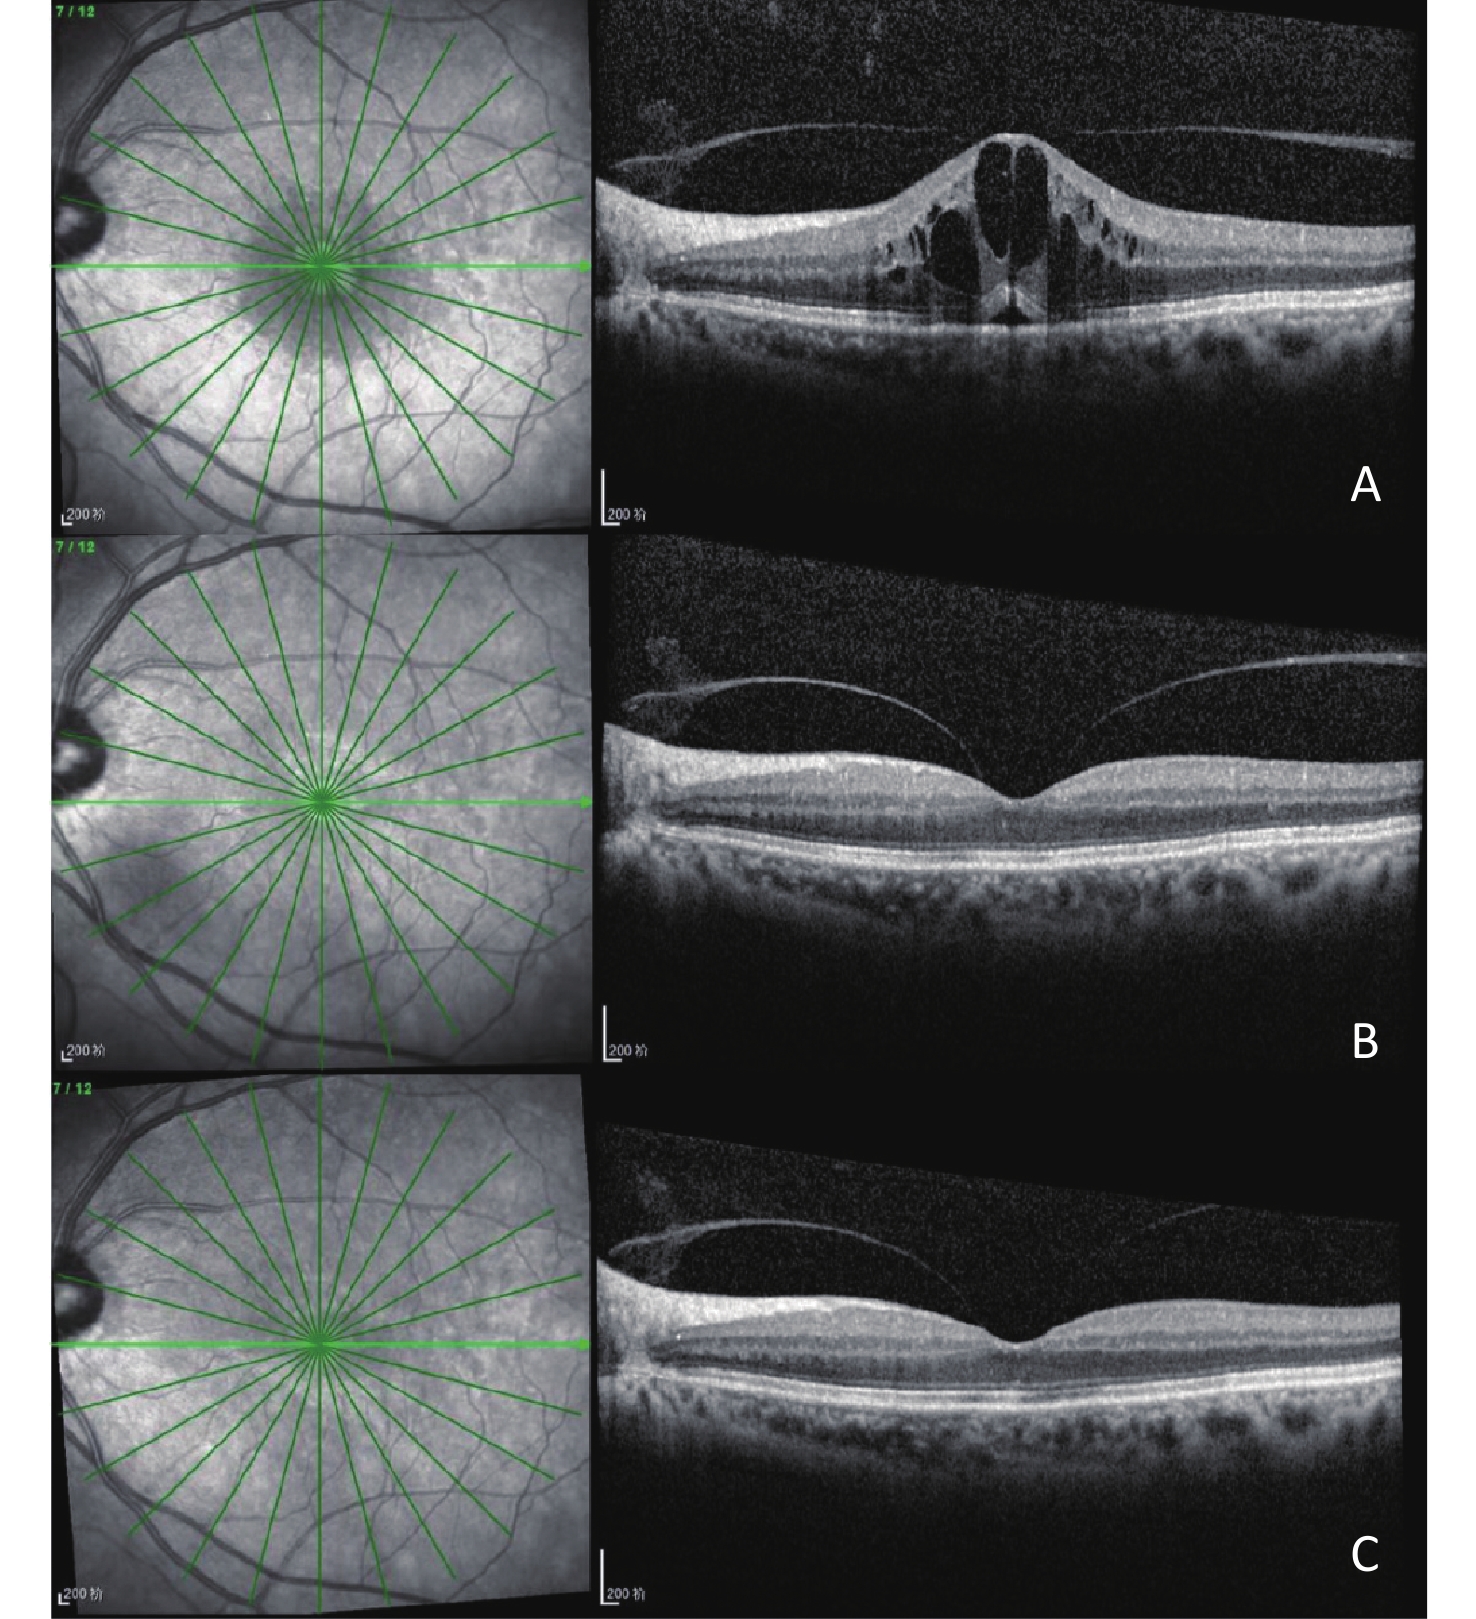

• The mean CMT was 703.00 ± 148.88 μm before Ozurdex implantation and decreased to 258.87 ± 37.40 μm, 236.25 ± 28.74 μm, and 278.00 ± 76.82 μm at 2 weeks, 1 month, and 3 months after implantation, respectively. The mean CMT decreased at all three follow-up time points after implantation compared with pretreatment, and the differences were statistically significant (P < 0.001). The difference in the reduction of CMT at 2 weeks after implantation compared with that at 1 month after implantation was statistically significant (P < 0.05) (Table 3, Figure 1B, and Figure 2A–C).

Figure 2.  Macular OCT changes before and after intravitreal Ozurdex injection in patients with Irvine-Gass syndrome. (A) is before injection, (B) is 1 month after injection, and (C) is 3 months after injection.